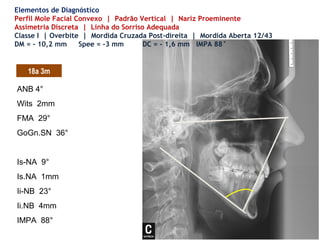

Elementos de Diagnóstico

Perfil Mole Facial Convexo | Padrão Vertical | Nariz Proeminente

Assimetria Discreta | Linha do Sorriso Adequada

18a 3m

Classe I | Overbite | Mordida Cruzada Post-direita | Mordida Aberta 12/43

DM = - 10,2 mm Spee = -3 mm DC = - 1,6 mm IMPA 88°

ANB 4°

Wits 2mm

FMA 29°

GoGn.SN 36°

Is-NA 9°

Is.NA 1mm

Ii-NB 23°

Ii.NB 4mm

IMPA 88°